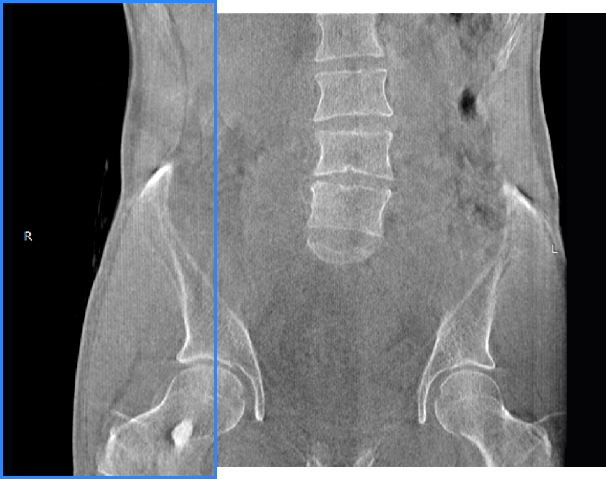

髋关节

关闭金属伪影校正

开启金属伪影校正